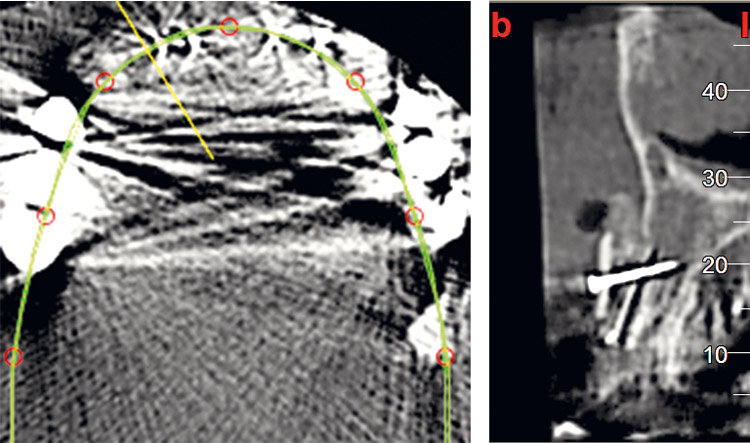

03 / 22 - Initial situation – CBCT image of the first quadrant

Three-dimensional augmentation with maxgraft® cortico - M.Sc. E. Kapogianni